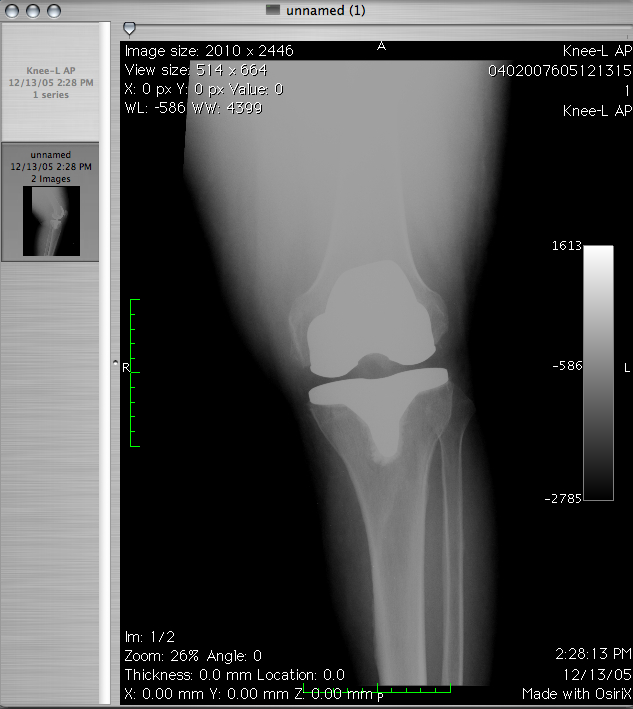

Medycyna rozwija się w bardzo szybkim tempie. Możemy dziś zaradzić wielu dolegliwościom. Tworzy się sporo …

Jedną z szybciej rozwijających się dziedzin jest rehabilitacja. Nie wiedzieliśmy kiedyś jak wielki potencjał w …